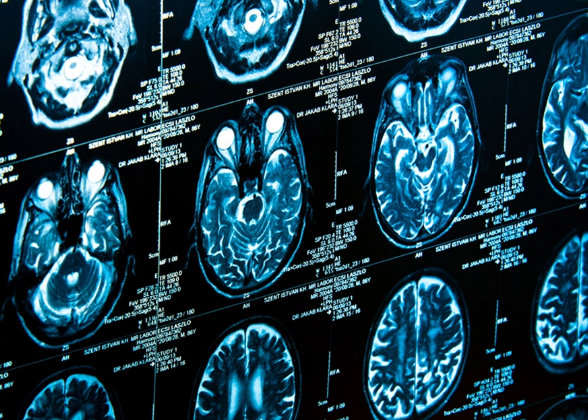

머리 CT 검사는 여러 상황에서 필요하다는 진단이 내려지곤 합니다. 일반적으로 의사가 이 검사를 권유하는 데는 다음과 같은 증상이 있을 수 있습니다.

CT는 일반 촬영과 조영제를 활용한 촬영으로 나뉘며, 조영제를 사용하는 경우 비용이 상승합니다. 조영제는 혈관을 통해 뇌의 혈류 흐름 등을 더 정밀하게 확인하기 위해 사용됩니다.